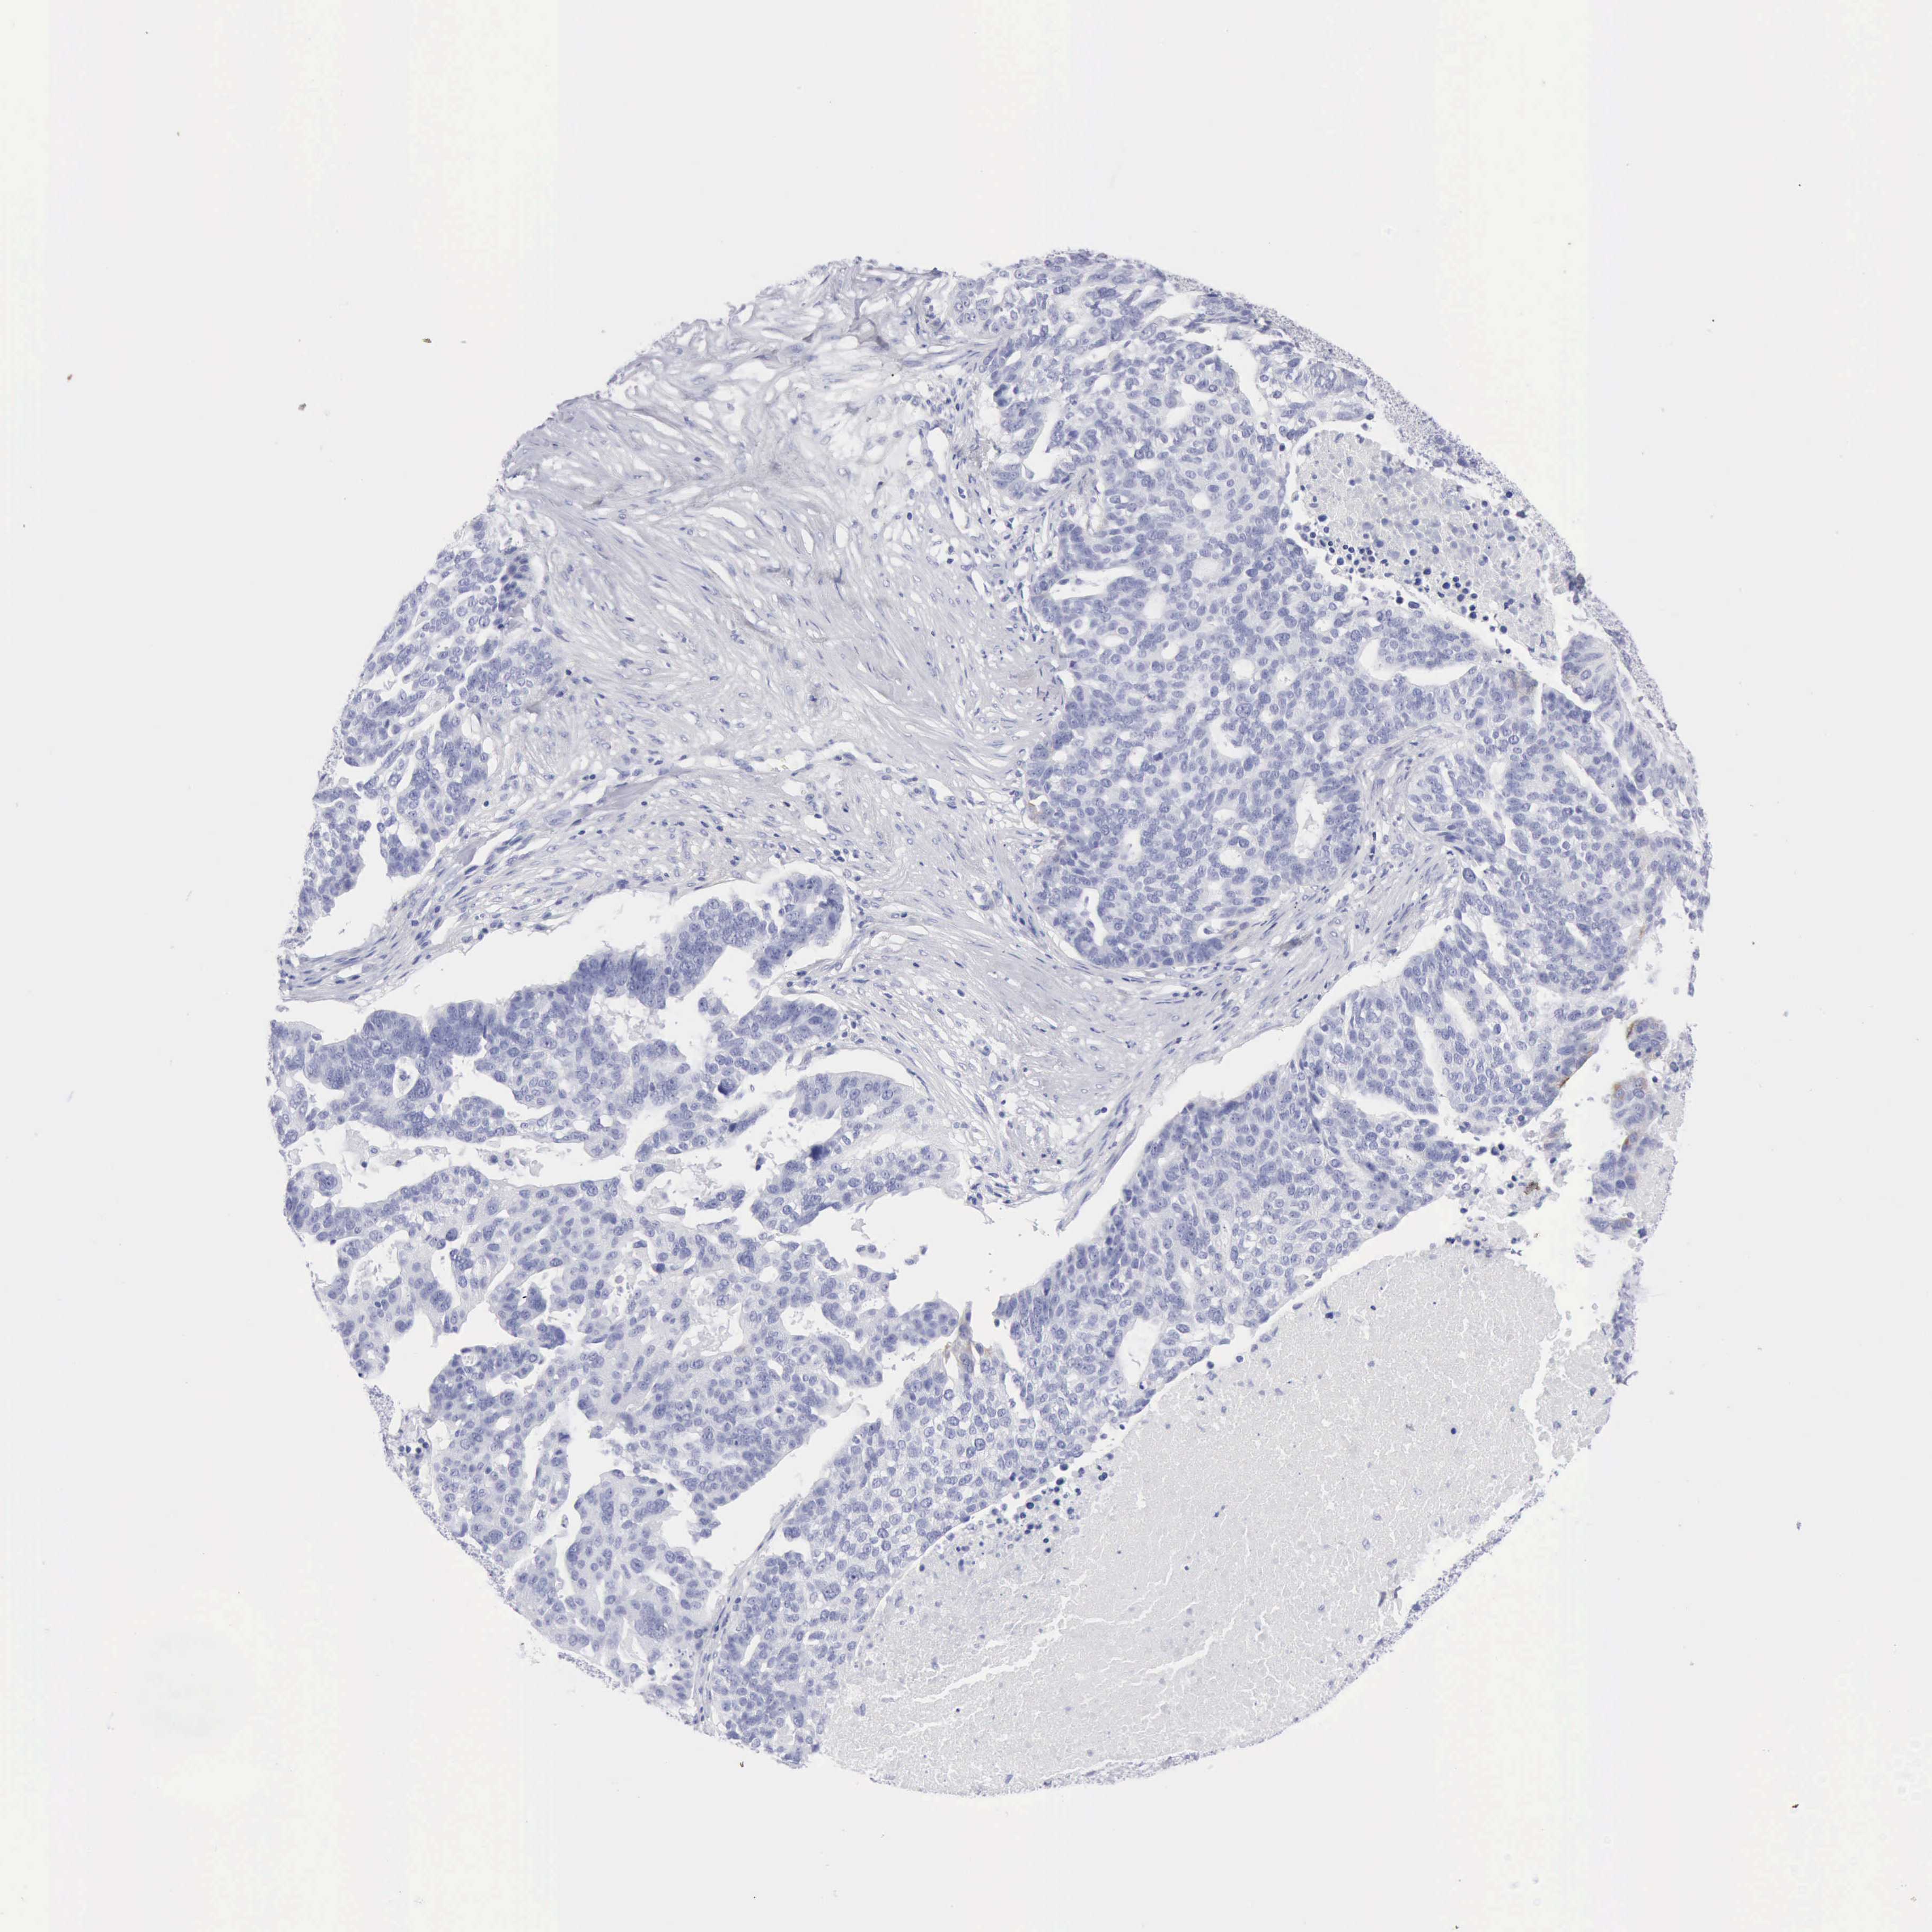

OVARIAN CANCER - Protein expressioni

A mouse-over function shows sample information and annotation data. Click on an image to view it in a full screen mode. Samples can be filtered based on level of antibody staining by selecting one or several of the following categories: high, medium, low and not detected. The assay and annotation is described here.

Note that samples used for immunohistochemistry by the Human Protein Atlas do not correspond to samples in the TCGA dataset.

Antibody stainingi

Antibody staining in the annotated cell types in the current human tissue is reported as not detected, low, medium, or high, based on conventional immunohistochemistry profiling in selected tissues. This score is based on the combination of the staining intensity and fraction of stained cells.

Each image is clickable and will lead to virtual microscopy that enables deeper exploration of all samples and also displays staining intensity scores, fraction scores and subcellular localization as well as patient and tissue information for each sample.

Antibody HPA059479

Antibody CAB000027

Antibody CAB000129

Antibody CAB080101

Cystadenocarcinoma, serous, NOS